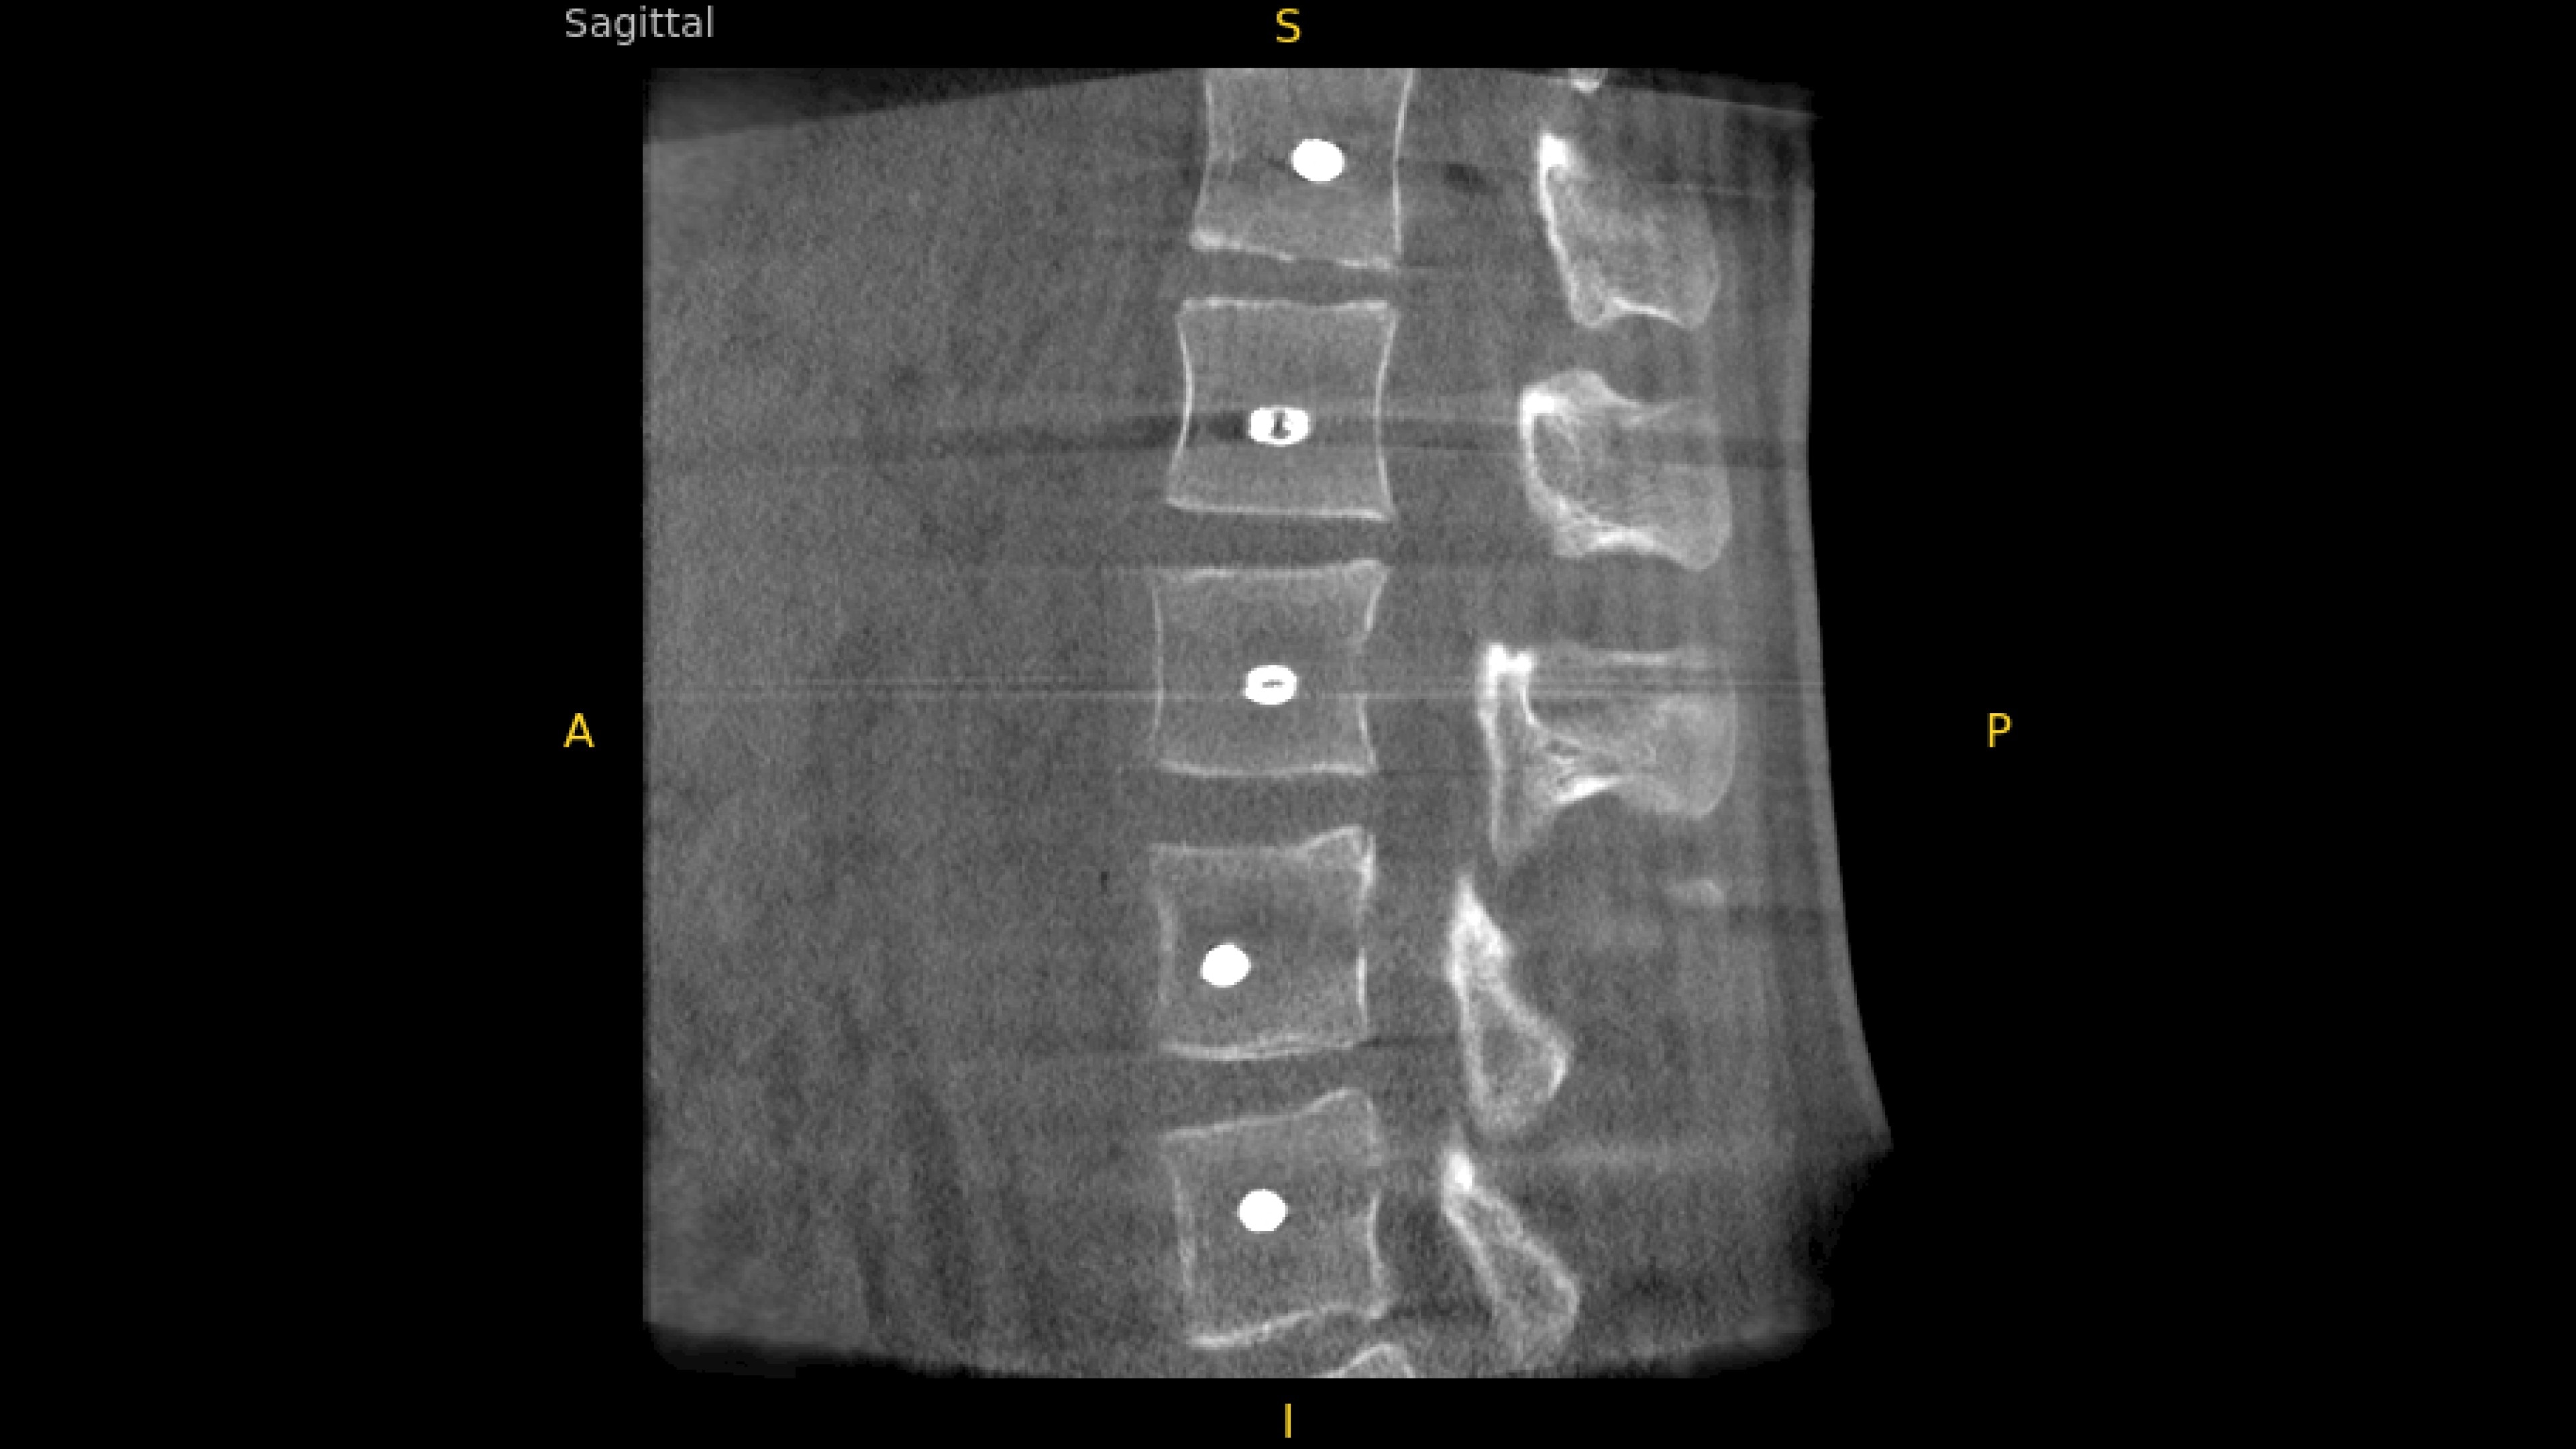

With OEC 3D, comprehensive imaging coverage of 19 cm x 19 cm x 19 cm 3D volumes and exceptional 2D images enables viewing several levels of the spine in the operating room.

The OEC 3D presents five perspectives: Axial, Coronal, Sagittal, MIP, and VR, on a 4K display for clear and detailed review of 3D volumes and 2D images